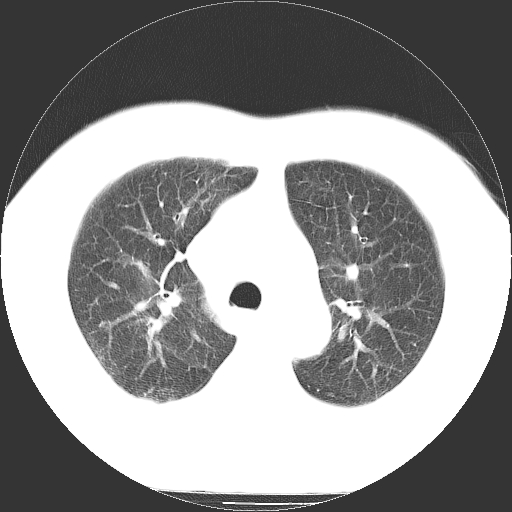

男,65岁,咳嗽、咳痰、发热5天。

慢支 肺间质纤维化合并感染!

支气管扩张合并感染,胸膜肥厚

考虑慢支并感染,肺间质纤维化。

两肺间质性炎症并感染

慢支,肺心病

支持慢性支气管炎伴感染,双侧少量胸腔积液.

两肺间质纤维化,支扩合并感染,双侧胸腔积液

感染,肺间质纤维化。

慢支 肺间质纤维化合并感染

支持慢性支气管、肺间质纤维化合并感染。

慢性支气管炎并感染,支扩,双侧少量胸腔积液.